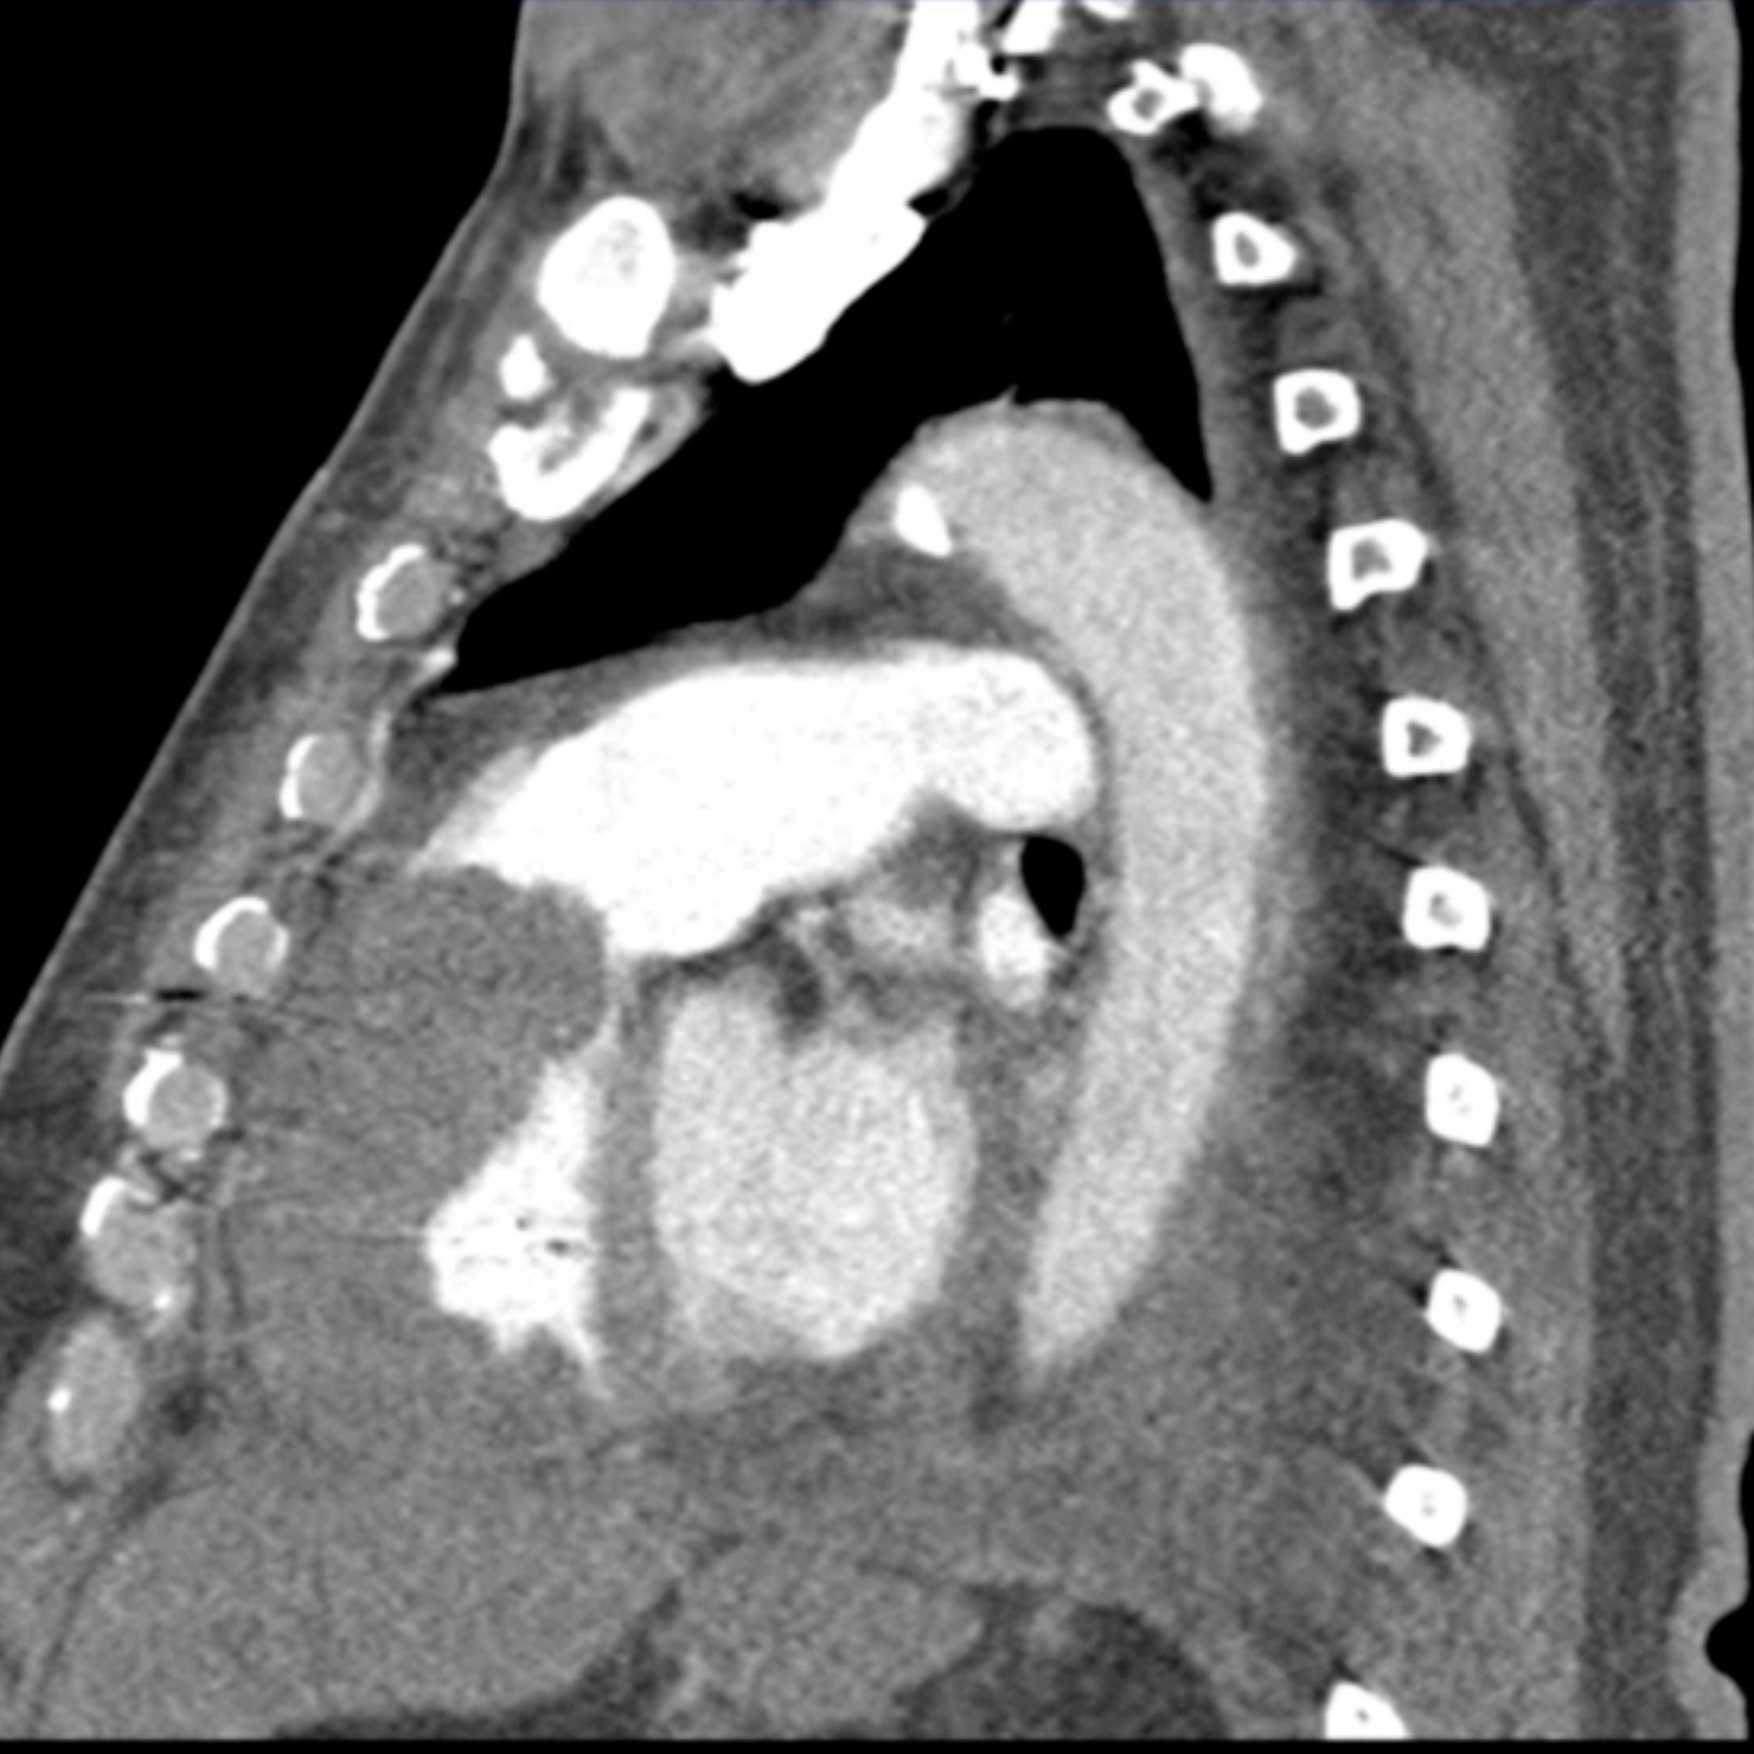

Primary Spindle Cell Carcinoma of the Right Ventricle